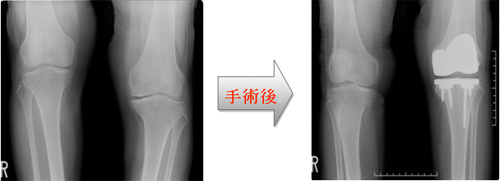

進行すると、人工関節に置換する手術をせざるを得なくなります。

手術療法

上記の保存療法では改善が見込めず、疼痛により日常生活に支障がある方が最終手段として行うものです。

I.人工膝関節置換術(Total Knee Arthroplasty = TKA)

人工膝関節置換術(TKA)はすり減った関節の表面を削り、金属と特殊ポリエチレンに入れ替えて痛みを楽にする手術です。膝全体を丸ごと取り替えるのではなく、表面1センチほどを入れ替えます。膝は太ももの骨とすねの骨とお皿の骨からできています。この3つの骨の表面を取り替えて間に特殊ポリエチレンを挟みます。同時にO脚も矯正し、膝のバランスが最高となる軽いX脚に整えます。これにより痛みの再発を予防し人工関節を長持ちさせます。

II.単顆人工関節置換術(Uni compartmental Knee Arthroplasty = UKA)

UKAは膝の内側のみを入れ替える手術です。UKAは膝の負担も少なく早い社会復帰が可能です。現在では、TKAにも劣らない成績が認められています。